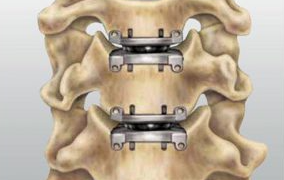

3.2 경추 디스크 교체

이 절차는 척추를 유합하는 대신 손상된 디스크를 인공 임플란트로 교체하여 경추의 자연스러운 움직임을 보존하는 것을 목표로 합니다. 이 옵션은 더 넓은 운동 범위를 유지하고자 하는 심각한 척추 퇴행이 없는 환자에게 적합할 수 있습니다.

절차:

의사는 ACDF 접근 방식과 유사하게 목 앞쪽 절개를 통해 영향을 받은 디스크에 접근합니다. 손상된 디스크를 제거하고 신경이나 척수를 압박하는 모든 구조를 제거합니다. 건강한 디스크의 자연스러운 움직임과 기능을 모방하도록 설계된 인공 디스크 임플란트를 빈 디스크 공간에 삽입합니다.

장점:

목의 운동 범위를 보존하여 인접 분절 퇴행의 위험을 줄입니다. 뼈 이식이나 척추 융합이 필요하지 않습니다.

단점:

인공디스크 임플란트의 장기내구성은 아직 연구가 진행 중이며, 임플란트 실패시 재수술이 필요할 수 있습니다.